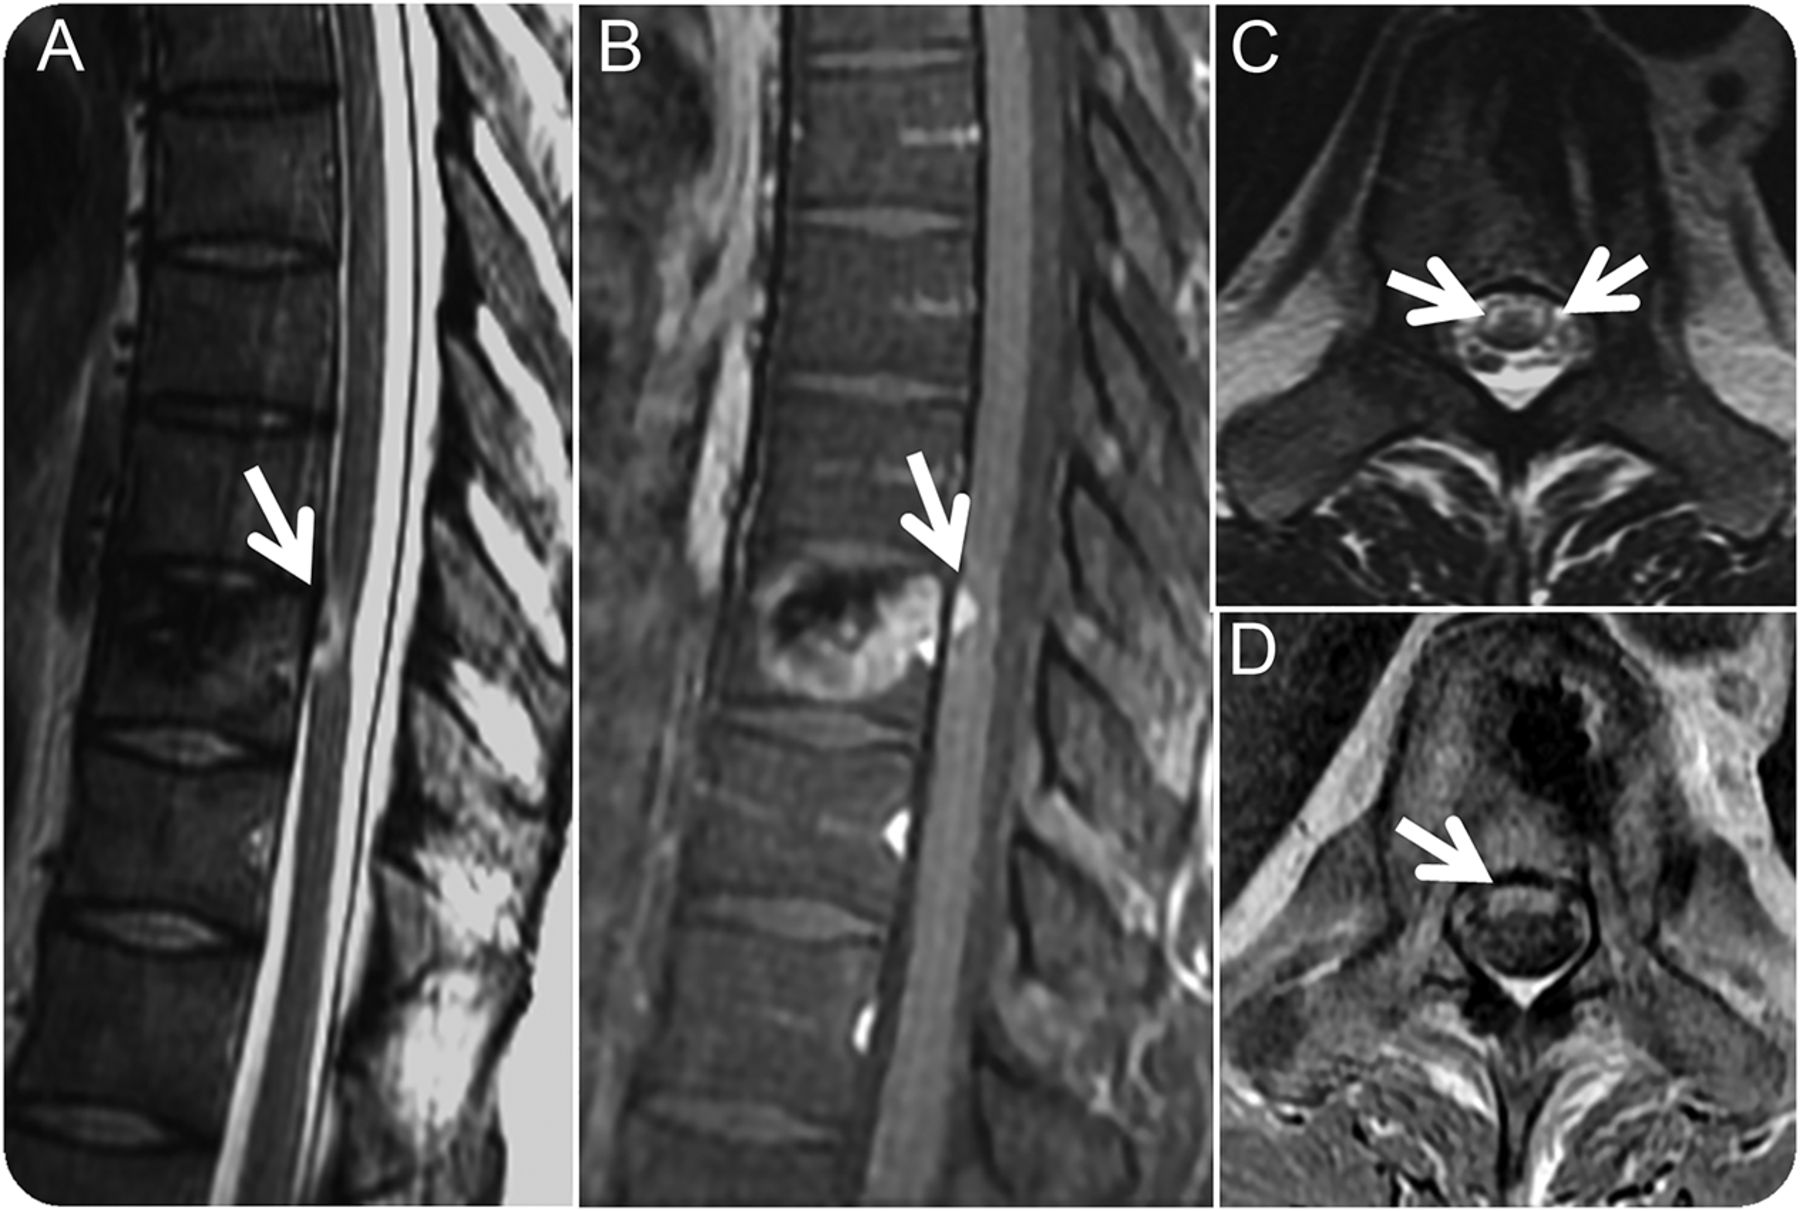

图2

后期随访postcryoablation

(安妮)三个月治疗后矢状T2 postgadolinium t1影像和轴向T2 postgadolinium t1影像:T2 hyperintensity和增强在腹侧胸线的水平消融(箭头,罪犯)。绳拴在硬脑膜出现罕见由于疤痕(箭头,A)。